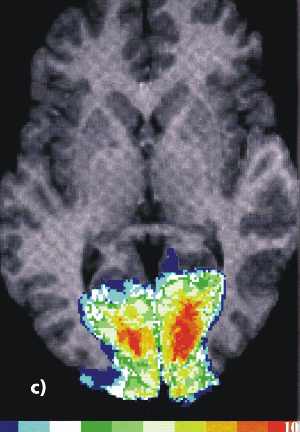

Die funktionellen Daten (bunt) in den beiden Bildern unten wurden mit der funktionellen Kernspintomographie (fNMR) gewonnen, bei der man Änderungen des NMR-Signals bei zunehmender Durchblutung eines aktiven Hirnareals auswertet. Als Beispiele für die Kombination von Bildern sind Überlagerungen von fNMR-Daten mit einem Kernspintomogramm (links) und mit einer graphischen Darstellung des Gehirns (rechts) abgebildet.

Aus: Forschen in Jülich, 1/2000, Forschungszentrum Jülich

fnmrh.jpg fnmr2h.jpg